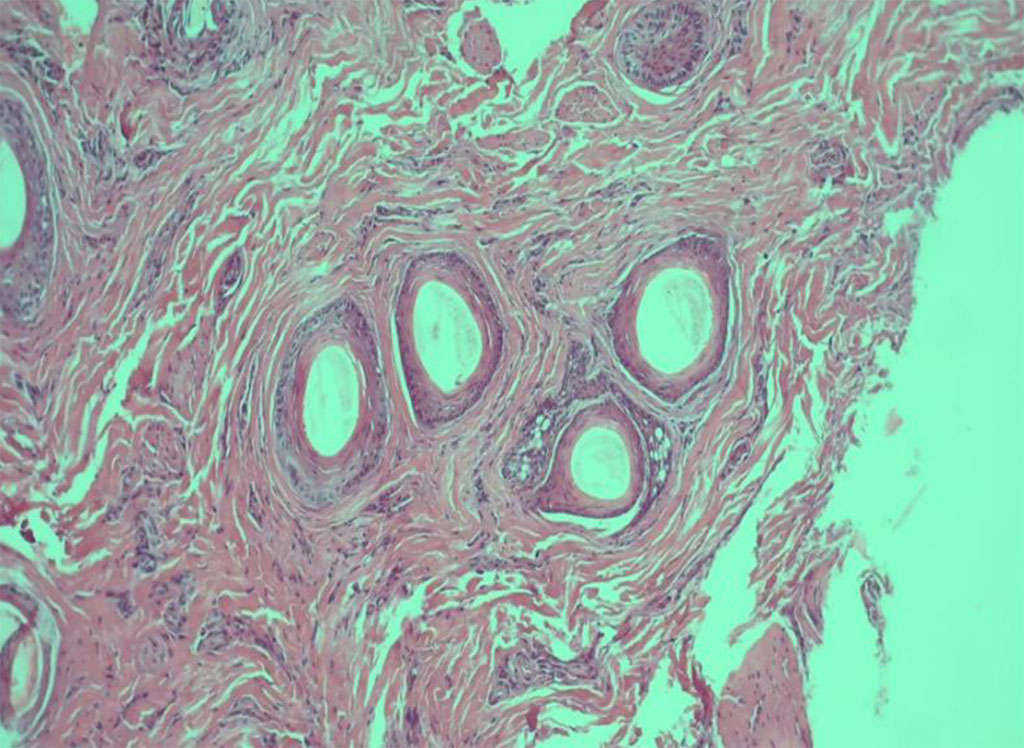

Considering the complexity of the clinical case after discontinuing systemic treatment, a histological examination was carried out in the areas of active inflammation in the vertex. The resulting biopsy revealed 17 sections of hair, mainly in the anagen phase, with a shaft thickness of 59-64 microns, preserved histological structure of the deeper structures of the follicle, hypotrophy of the follicular epithelium and perifollicular fibrosis at the level of the infundibulum, with the formation of gaps similar to the «Max-Joseph space», mild lymphocytic infiltration, not penetrating the epithelium; the number of sebaceous glands was reduced.

Fig.3 Histological picture of LPP (staining with hematoxylin and eosin)

Based on the totality of features, the histological picture corresponds to the follicular form of lichen planus. The treatment regimen was corrected; intralesional corticosteroid injections were prescribed once a month, oral cyclosporine at a dose of 3 mg/kg per day. During a treatment period of 3 months, positive dynamics were noticed: itching subsided, peripheral growth of lesions, the phenomena of perifollicular erythema and hyperkeratosis decreased significantly, and hair loss stopped. Treatment was continued with cyclosporine until the skin rashes were completely stabilized.